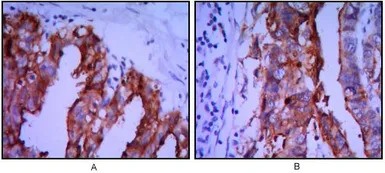

IHC-P analysis of ovarian cancer (A), stomach cancer (B) using GTX82823 Placental Alkaline Phosphatase antibody [3E5].